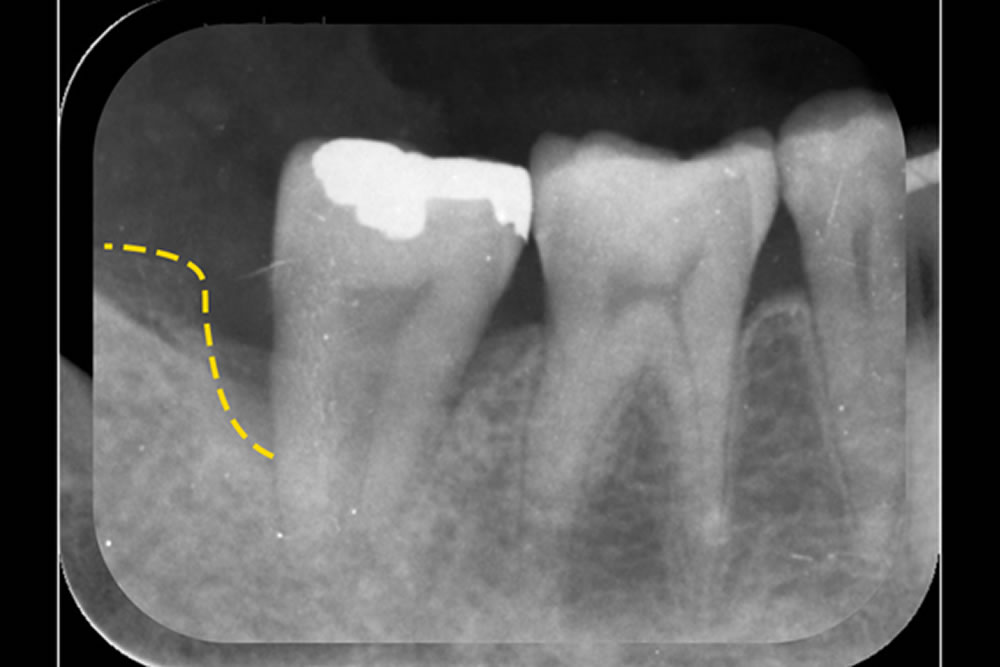

初診時(上写真)、右下6番目の歯は今にも抜け落ちそうな状態でしたが、重度歯周病治療【MINST】によって、症状を改善し、術後1年後(下写真)には歯周組織もしっかりと再生しました。

※外科処置なし・再生材料も使用しておりません。